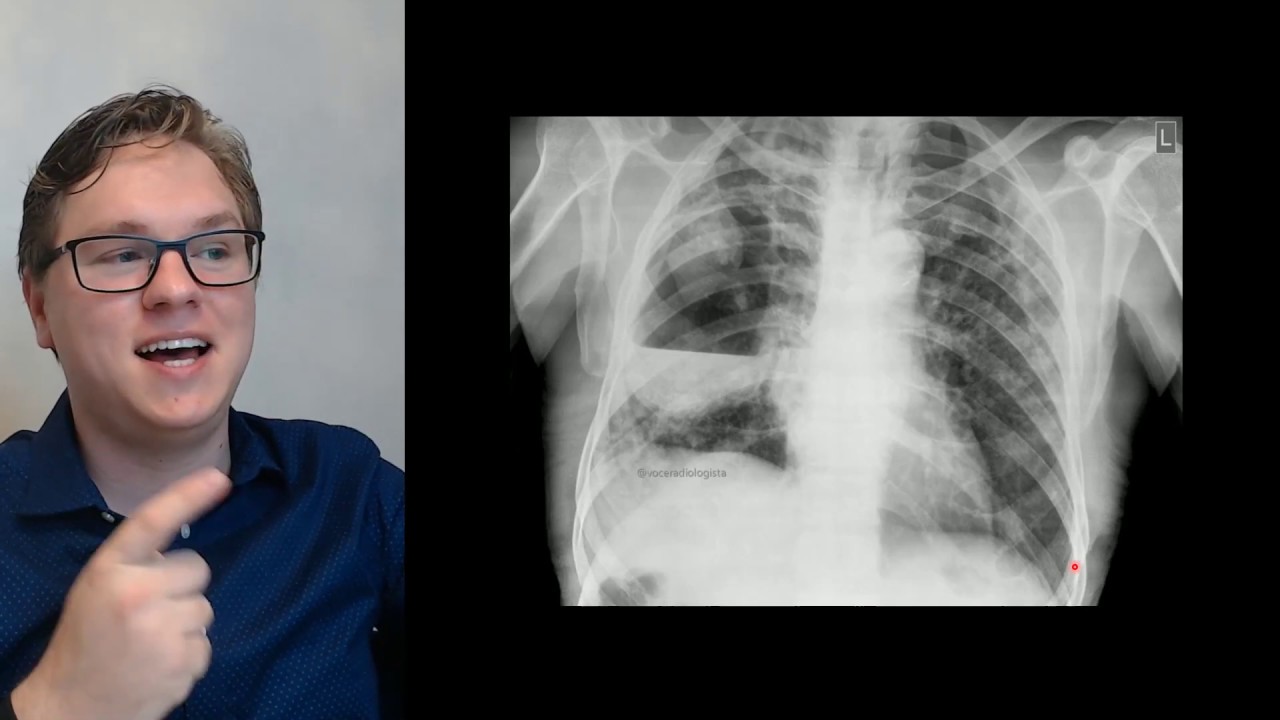

e a tuberculose a famigerada tuberculose quanto tuberculose classicamente vai dar imagens como essa daqui de escalação repara que o parêntema pulmonar o alvéolo ele tem a mas ele não é preto ele é cinza escuro tá vendo aqui é o velos normais a escalação ela sim é preta como vocês estão vendo aqui porque aqui não tem parede alvéolo aí é só ar é uma cavidade tá então a cavidade com suas paredes como vocês podem ver aqui mas é uma cavidade mas o que que tem mais além de escavação na tuberculose Eu tenho um nódulos a tuberculose

galera é uma doença disseminada por via aérea Isso significa que o bacilo ele chega pelo broto e ele vai fazer um nódulo lá no final do broke tá é o nólo quem chama de centro logo lá porque lá no finalzinho do pulmão ele tem uma estrutura arquitetônica que é o que dá a composição do pulmão chamado glóbulo secundário no centro desse lóbulo secundário eu tenho o bronquillo terminal e é lá que o nódulozinho da tuberculose vai se formar tá então eu tenho esse monte de nódulozinho aqui ó que representa uma doença disseminada por via aérea

só tuberculose faz isso não mas no nosso meio tuberculose é o principal diagnóstico a ser considerado Quando você vê esse tipo de nódulo esse tipo de nódulo ele tem uma característica peculiar que é o aspecto ramificado é como se tivesse uma cabeça e duas orelhinhas uma cabeça de um Mickey por exemplo aqui tá vindo é um nódulo e ele tem ó uma ramificação duas orelhinhas é bem discreto é bem discreto isso aqui novamente eu tenho uma cabeça e duas orelhinhas isso aí é o aspecto ramificado que só vai acontecer medicina nem sempre nem nunca mais

é quase para todo mundo das infecções de via respiratória dos nódulos centro-lablares então escalação é importante mas nódulo centro lombular ramificado a gente chama essa ramificação com aspecto de árvore em brotamento olha aqui ó árvore brotamento Esse aspecto aí é muito característico e eu vou dar uma notícia para vocês que não é tão boa para quem não tava nessa aula tuberculose muitas vezes não vai ter a escalação vai ter só esse nódulo ramificado [Música]